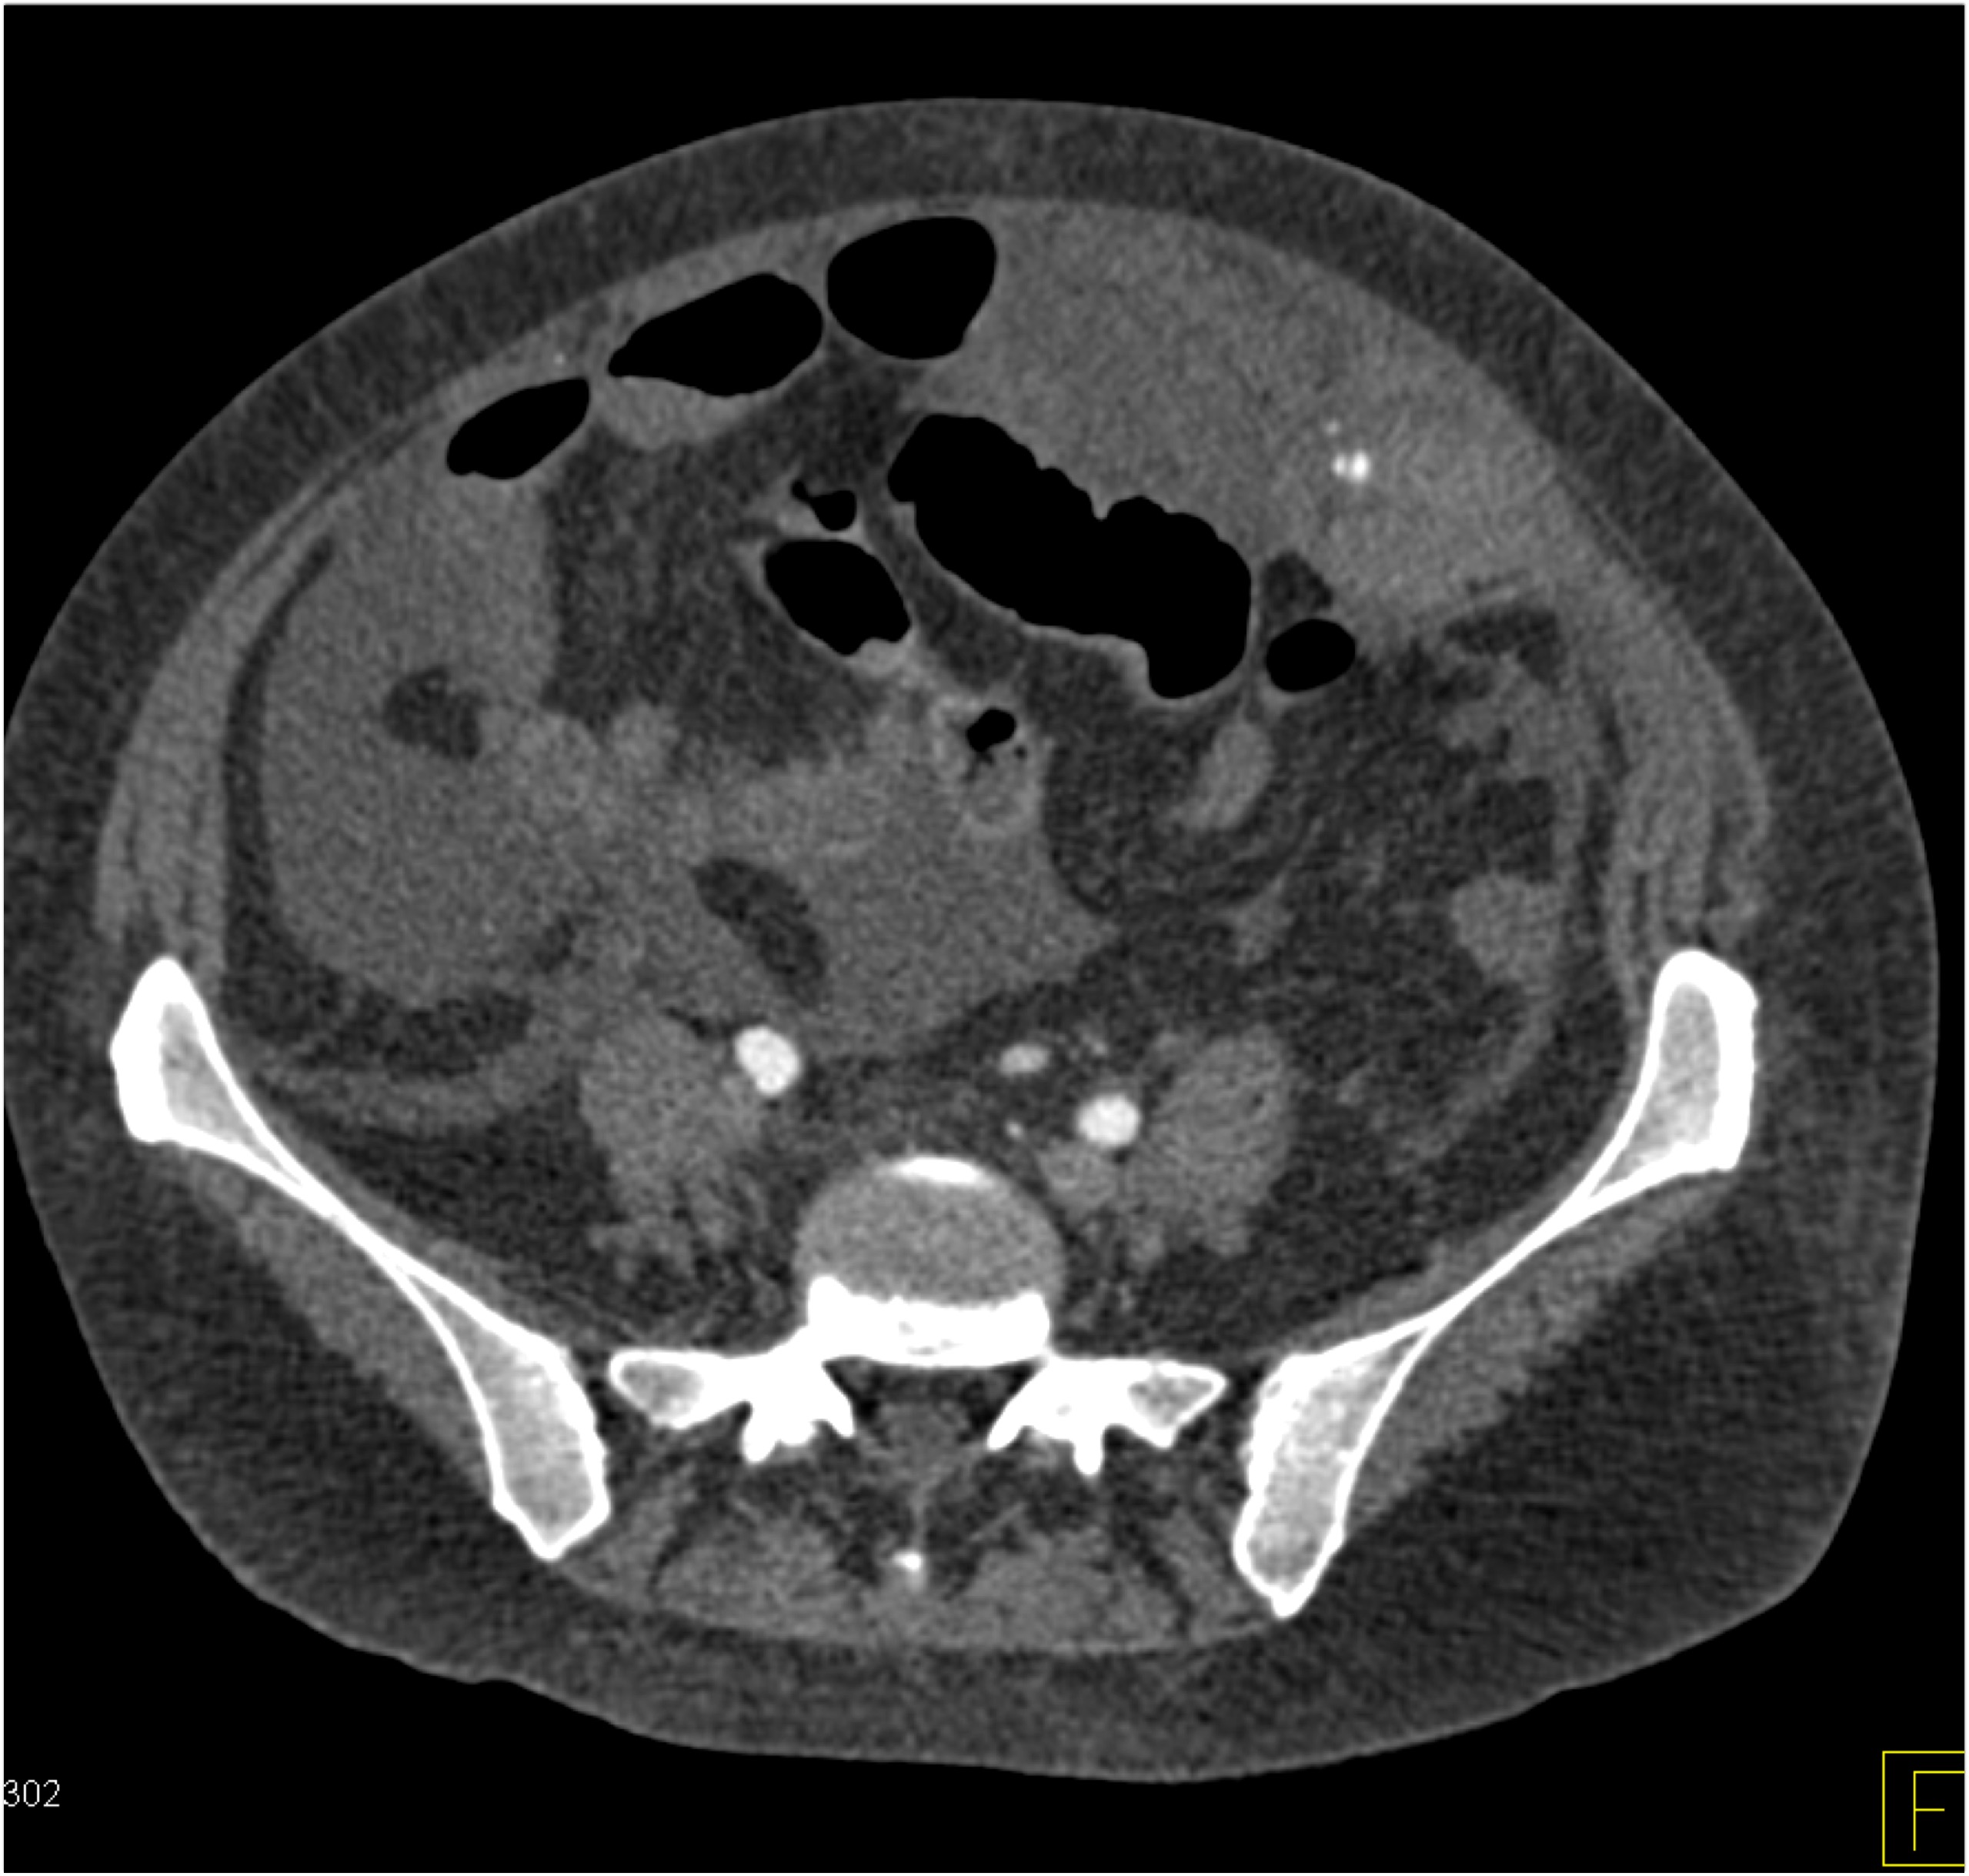

1) The best diagnosis in this patient with RLQ pain and fever is?

salmonella infection

acute appendicitis

Crohn’s disease

TB of the ileum